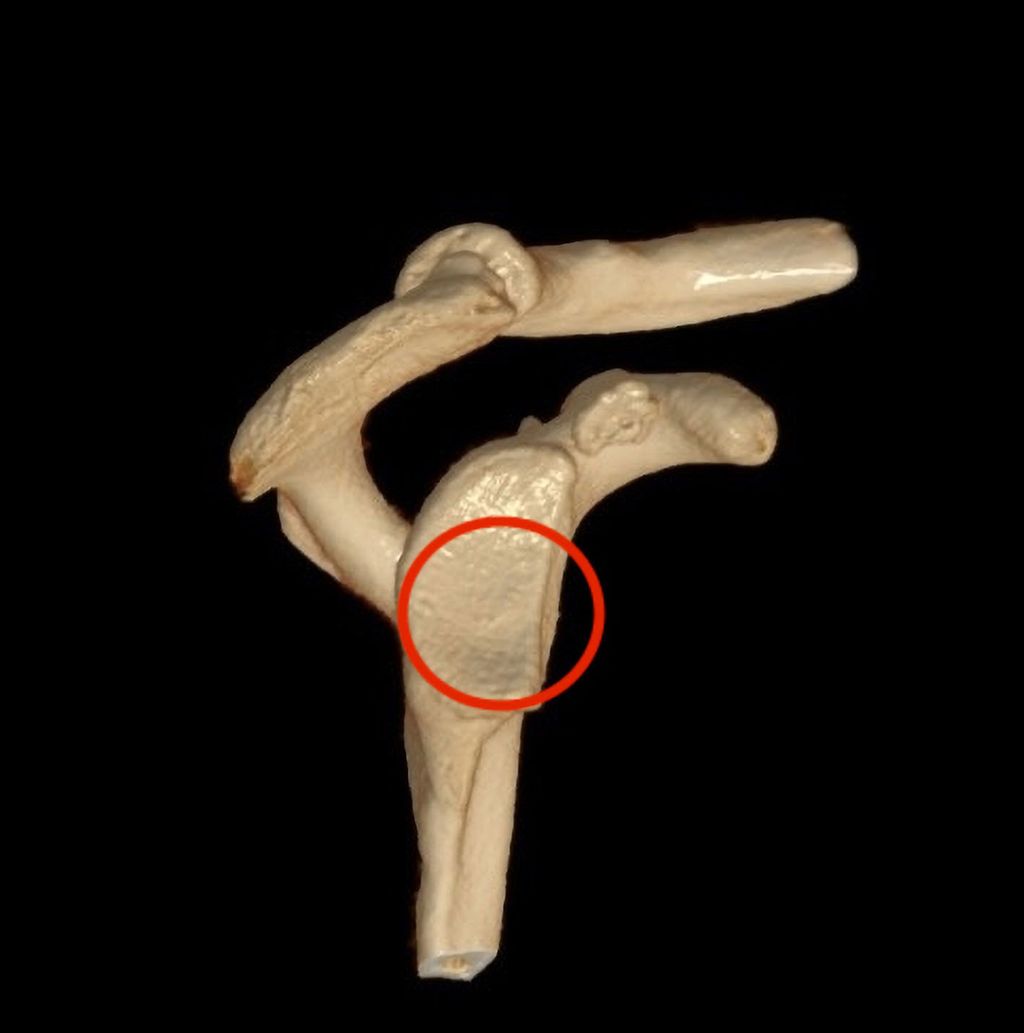

Therapie des Hill-Sachs-Defekts

Große Hill-Sachs-Läsionen und bipolare Läsionen (Glenoid und Humeruskopf) führen häufig zu Rezidivluxationen. Durch das Einhaken des humeralen Knochendefektes am Pfannenrand kommt es zu einer Luxation des Gelenkes („engaging Hill-Sachs“).118,119 Eine „engaging Hill-Sachs-Läsion“ kommt in ca. 7% aller Fälle mit rezidivierender Schulterluxation vor.87 Zusätzlich zur arthroskopischen Bankartoperation oder einem Knochenblockverfahren zur Behandlung eines glenoidalen Knochendefektes kann eine Remplissage die Rezidivgefahr zusätzlich vermindern.120,121 Bei kombinierten bipolaren Defekten sollte nach Kadaverstudien bereits bei einem humeralen Defekt von 19% des Oberarmkopfdurchmessers und bei Glenoiddefekten von 10% der Glenoidbreite eine knöcherne Rekonstruktion angestrebt werden122 (Abb. 8). Im Rezidivfall sollte bei biploaren Defekten und bei einem großen „engaging Hill-Sachs-Defekt“ zusätzlich zum Glenoidaufbau auch an eine Auffüllung des humeralen Defektes mit einem osteochondralen Allograft gedacht werden.109,123 Damit sind gute klinische Ergebnisse zu erzielen, wenngleich doch eine nicht unbeträchtliche Komplikationsrate mit großen Allografts beschrieben ist (20,5–42,5%).

Abb. 8: Bei kombinierten bipolaren Defekten sollte bereits bei einem humeralen Defekt von 19% des Oberarmkopfdurchmessers und bei Glenoiddefekten von 10% der Glenoidbreite eine knöcherne Rekonstruktion angestrebt werden